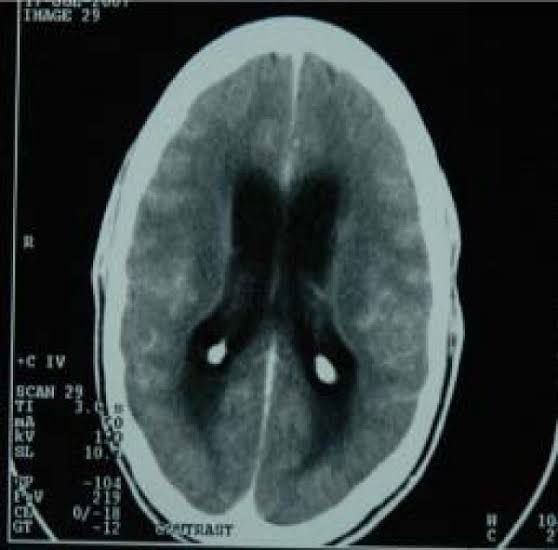

Tuberculous Meningitis (TBM) is a form of meningitis characterized by inflammation of the membranes (meninges) around the brain or spinal cord and caused by a specific bacterium known as Mycobacterium tuberculosis. In TBM, the disorder develops gradually.